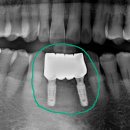

대구 시지바름플란트치과의원입니다. 치아가 흔들려요 시지치과 최근 위와 같은 주소로... 환자분께 가장 잘 맞았던 임시치아와 같은 형태로 기공소에 보철 기공을 의뢰하고 나서, 보철을 올려주기만 하면...

대구 시지바름플란트치과의원(20240920)

자연치아를 살리고 싶어서 찾고 찾아보다가 멀리서 잠실 더바름치과 까지 왔습니다. 꼭 살리고... 좋은 보철물을 위해서는 치과의사의 노하우도 중요하지만 *. 본을 잘 뜨고 *. 기공소에서 좋은 보철물을...

Dentistry, Combination ART & SCIENCE(20241216)